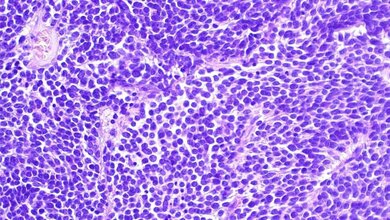

Die nun publizierte Studie nutzte modernste Methoden wie das Single Cell Sequencing, um einzelne Tumorzellen genomweit zu analysieren und ihre molekularbiologischen Eigenschaften zu beschreiben. Dabei zeigte sich, dass Ependymome sehr heterogen sind, also aus vielen Zellen mit unterschiedlichen Eigenschaften bestehen, was die Behandlung erschwert. Das Forscherteam untersuchte im Zuge seiner Arbeit Zellen von Tumoren mit guter Prognose, ebenso wie solche mit aggressiven Verläufen. Ein Großteil der Patienten/-innen, deren Tumoren untersucht wurden, wurden von der MedUni Wien in die Studie eingebracht (20 von insgesamt 28).

Eine wesentliche Erkenntnis der Forscher/-innen bestehe im Nachweis, dass Ependymomzellen aus einer bestimmten Stammzellnische des Gehirns entstehen. Damit weisen sie auch oft Eigenschaften von Stammzellen auf. Stammzellen besitzen die Fähigkeit, andere Körperzellen zu ersetzen und zu Körperzellen mit verschiedenen Funktionen (z.B. Nervenzellen) heranzureifen (Ausdifferenzierung). Solange sie noch unreif, also undifferenziert sind, können sie sich im Prinzip unbegrenzt vermehren. Sind die Zellen entartet, entsteht eine besonders aggressive Form von Krebs. Johannes Gojo, Facharzt und Forscher an der Universitätsklinik für Kinder- und Jugendheilkunde der MedUni Wien und des Universitätsklinikums AKH Wien sowie am Institut für Krebsforschung der MedUni Wien, Mitglied des CCC sowie des Comprehensive Center for Pediatrics (CCP) der MedUni Wien und des AKH Wien und Erstautor der Studie betont: „Wir haben gesehen, dass die einzelnen Zellen von Ependymomen innerhalb des Tumors verschiedene Entwicklungsstadien durchlaufen. Jene mit aggressivem Verlauf weisen viele unreife Zellen auf, das heißt, sie sind Stammzellen sehr ähnlich. Tumoren, bei denen sich ein Großteil der Zellen in einem ausgereifteren Zustand befand, zeigten eine günstigere Prognose. Dieses Ergebnis könnte uns einen Ansatzpunkt für neue Therapiekonzepte liefern.“ Es erklärt außerdem, warum sich Ependymome bei Kindern häufig aggressiver verhalten als bei Erwachsenen: Bei ihnen ist der Anteil an undifferenzierten, stammzellartigen Ependymomzellen höher als bei Erwachsenen.